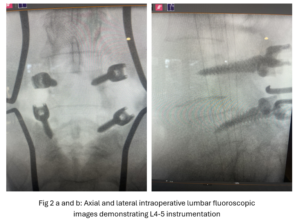

Figs 1a,b: T2-weighted sagittal and axial MRI demonstrating (red arrow) a large right L4-5 foraminal synovial cyst. Note the grade 1 spondylolisthesis (blue arrow)

This 54-year-old female with a long history of low back pain presents with three weeks of a progressive right footdrop with associated numbness and tingling of the right leg. In addition, she had right lateral hip pain down to the dorsum of her foot. She first noticed her right foot slapping the floor when she walked. She had no prior trauma or unusual activity before this began. Her chiropractor, who had treated her back pain for a long time, first noticed the foot drop and referred her for further evaluation. She presented with ⅖ strength in her right dorsiflexor. MRI revealed a large right L4-5 foraminal synovial cyst with some mass-effect on the thecal sac. (Fig. 1) She also had an associated grade 1 spondylolisthesis. Because the cyst was more foraminally-oriented, it had the majority of its effect on the right L4 nerve root. It was felt the patient required surgery to attempt to reverse her weakness. We performed a decompressive laminectomy at L4, removing the inferior facet process on the right in order to gain lateral and foraminal access to the right L4 nerve root. In the lateral recess there was a heap of inflammatory tissue which we entered, revealing the cyst. The medial wall was stuck to the dura. We internally decompressed the cyst which was mainly gelatinous material with some fluid. We dissected and removed as much of the cyst we could safely remove but left the medial wall for fear of removing it would cause a CSF leak, upon removing the bulk of the cyst we encountered anteriorly the descending and exiting right L4 nerve root which was purplish in color and clearly inflamed. We performed a generous foraminotomy of the right L4 as well as the right L5 nerve root. We also performed an instrumented fusion at L4-5 (Fig. 2).